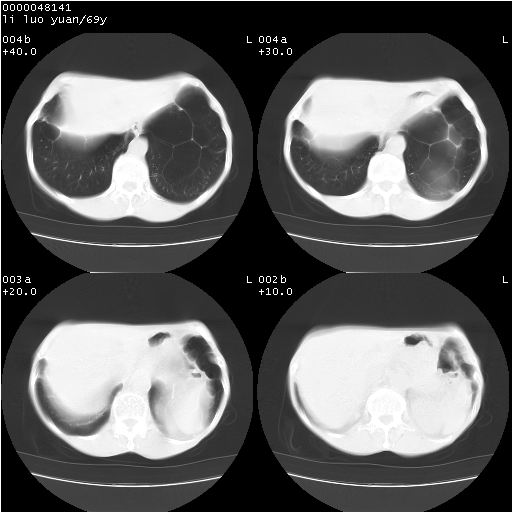

临床资料:老年患者,咯血、消瘦

影像表现:桶状胸,双肺纹理纤细、紊乱,透过度增高,肺野内可见多发、散在、大小不等的无壁高透过影,右肺中叶外侧段分叶样软组织占位,左上肺纤维索条样密度影,相应层面左侧胸腔轻度萎陷,纵隔左移。

影像诊断:1、慢支、肺气肿、双下肺野肺大泡形成

2、左上肺陈旧性肺结核

3、右肺中叶外侧段占位 考虑肺ca可能性较大、建议增强及痰检脱落细胞